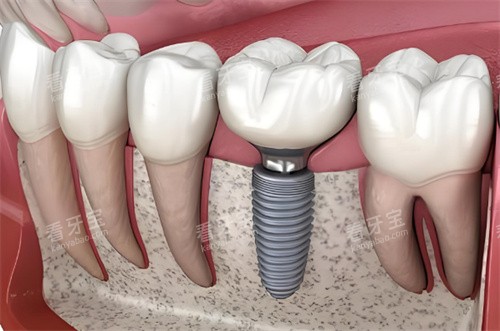

传统的RBM处理方式已大规模转向更为较高的SLA大颗粒喷砂加酸蚀技术,这使得植体与牙槽骨的结合效率显著提升。

韩国植体品牌之所以广受欢迎,核心在于其设计思路贴合东方人的骨质特点。

东方人的牙槽骨通常相对较薄且骨密度差异较大,韩系品牌通过微螺纹设计和锥形连接方式,有效解决了种植初期的稳定性问题。

奥齿泰的优势在于其独特的复合表面处理技术,能够模拟人体骨组织的结构,诱导骨细胞快速生长。

其比较准的莫氏锥度连接能够有效防止细菌侵入,减少植体周围炎的发生率。

在稳定性方面,奥齿泰的自攻性设计使得医生在植入时能获得良好的初期扭矩,非常适合即刻种植需求。

登腾植体采用的是大螺纹设计,这种结构能增加与骨组织的接触面积,从而提高初期稳定性。

其SLA表面处理工艺成熟,骨结合周期通常缩短至八周到十周。

纽百特植体的底部设计有助于在不同骨质条件下都能获得稳定的抓取力。